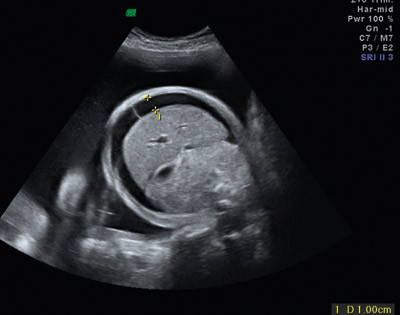

En kvinne kan bli immunisert mot blodtypeantigener som hun selv mangler, og som fosteret har arvet fra far. Immuniseringen kan gi hemolyse av barnets erytrocytter (hemolytisk sykdom hos foster og nyfødt). Hemolysen kan føre til at barnet utvikler anemi, som kan føre til hydrops foetalis, som ubehandlet kan ha fatalt forløp (fig1). Før fødselen vil bilirubinet som frigjøres ved hemolysen, passere placenta og bli konjugert og utskilt av mor, men hos den nyfødte vil ukonjugert bilirubin akkumuleres fordi leveren ikke har tilstrekkelig konjugeringskapasitet. Ukonjugert bilirubin kan trenge inn i basalgangliene og gi varige nevrologiske skader.

Figur 1  Ultralydbilde, tverrsnitt av føtal abdomen som viser ascites ved hydrops foetalis